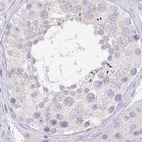

Immunohistochemistry analysis in human salivary gland and colon tissues using Anti-PRR27 antibody. Corresponding PRR27 RNA-seq data are presented for the same tissues.